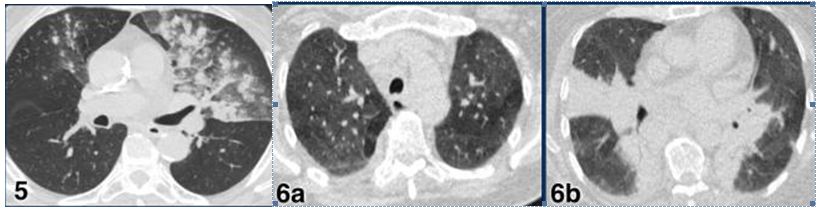

CO-RADS 3: Hình 5 & 6

Hình 5:

Trường hợp 1: Tổn thương GGO bên phải (duy nhất 1 vị trí). PCR (-) với COVID 19

Trường hợp 2: Tổn thương GGO duy nhất phân thùy sau dưới phải (vòng tròn)

Trường hợp 3: Tổn thương GGO duy nhất khu trú phân thùy sau phải (mũi tên)

Trường hợp 4: Tổn thương GGO duy nhất phân thùy sau dưới phải (vòng tròn)

Hình 6:

Trường hợp 5: Tổn thương nhiều ổ đông đặc kết hợp GGO. PCR (-) với COVID 19

Trường hợp 6a & b: Tổn thương đồng đặc cả 2 bên kết hợp GGO lan tỏa (BN Nhiễm cúm A)